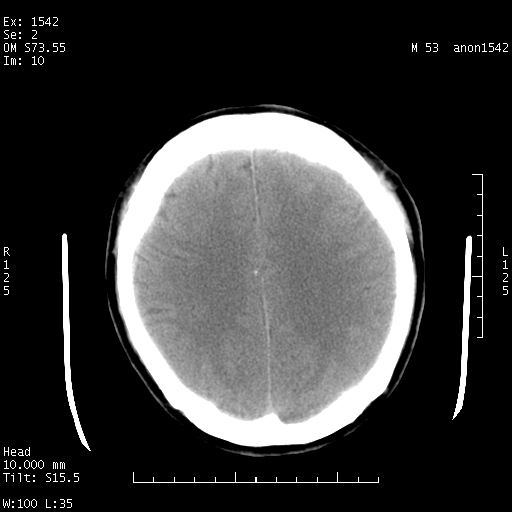

标题: CT10811:M53Y,头痛一月.其它没有什么 [打印本页]

标题: CT10811:M53Y,头痛一月.其它没有什么

左侧鞍旁不规则低密度,此区域和侧脑室有液平。若无外伤史。考虑左侧鞍旁表皮样囊肿自发破溃。

鞍旁颞叶低密度灶.其中散在空气影.还有侧脑室.是否考虑脑脓肿(请提供病史情况)

1.支持考虑左侧鞍旁表皮样囊肿自发破可能;

2.转移待排,其他?

有肿瘤样病变破溃,沿外侧裂生长,为什么不考虑胆脂瘤?

考虑左侧鞍旁表皮样囊肿自发破溃。